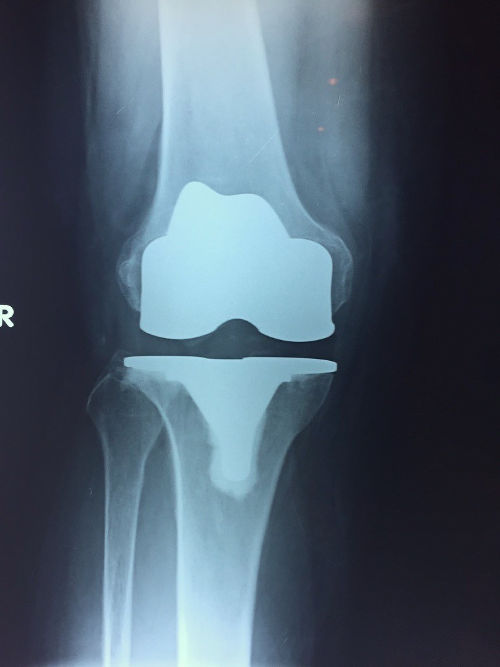

εικ. ακτινογραφία γόνατος με Ολική Αρθροπλαστική. Πλήρης αντικατάσταση της άρθρωσης